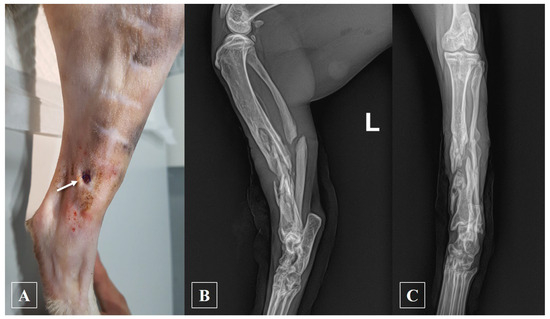

2.1. History and Clinical Examination

2.2. Anesthesia and Surgical Treatment